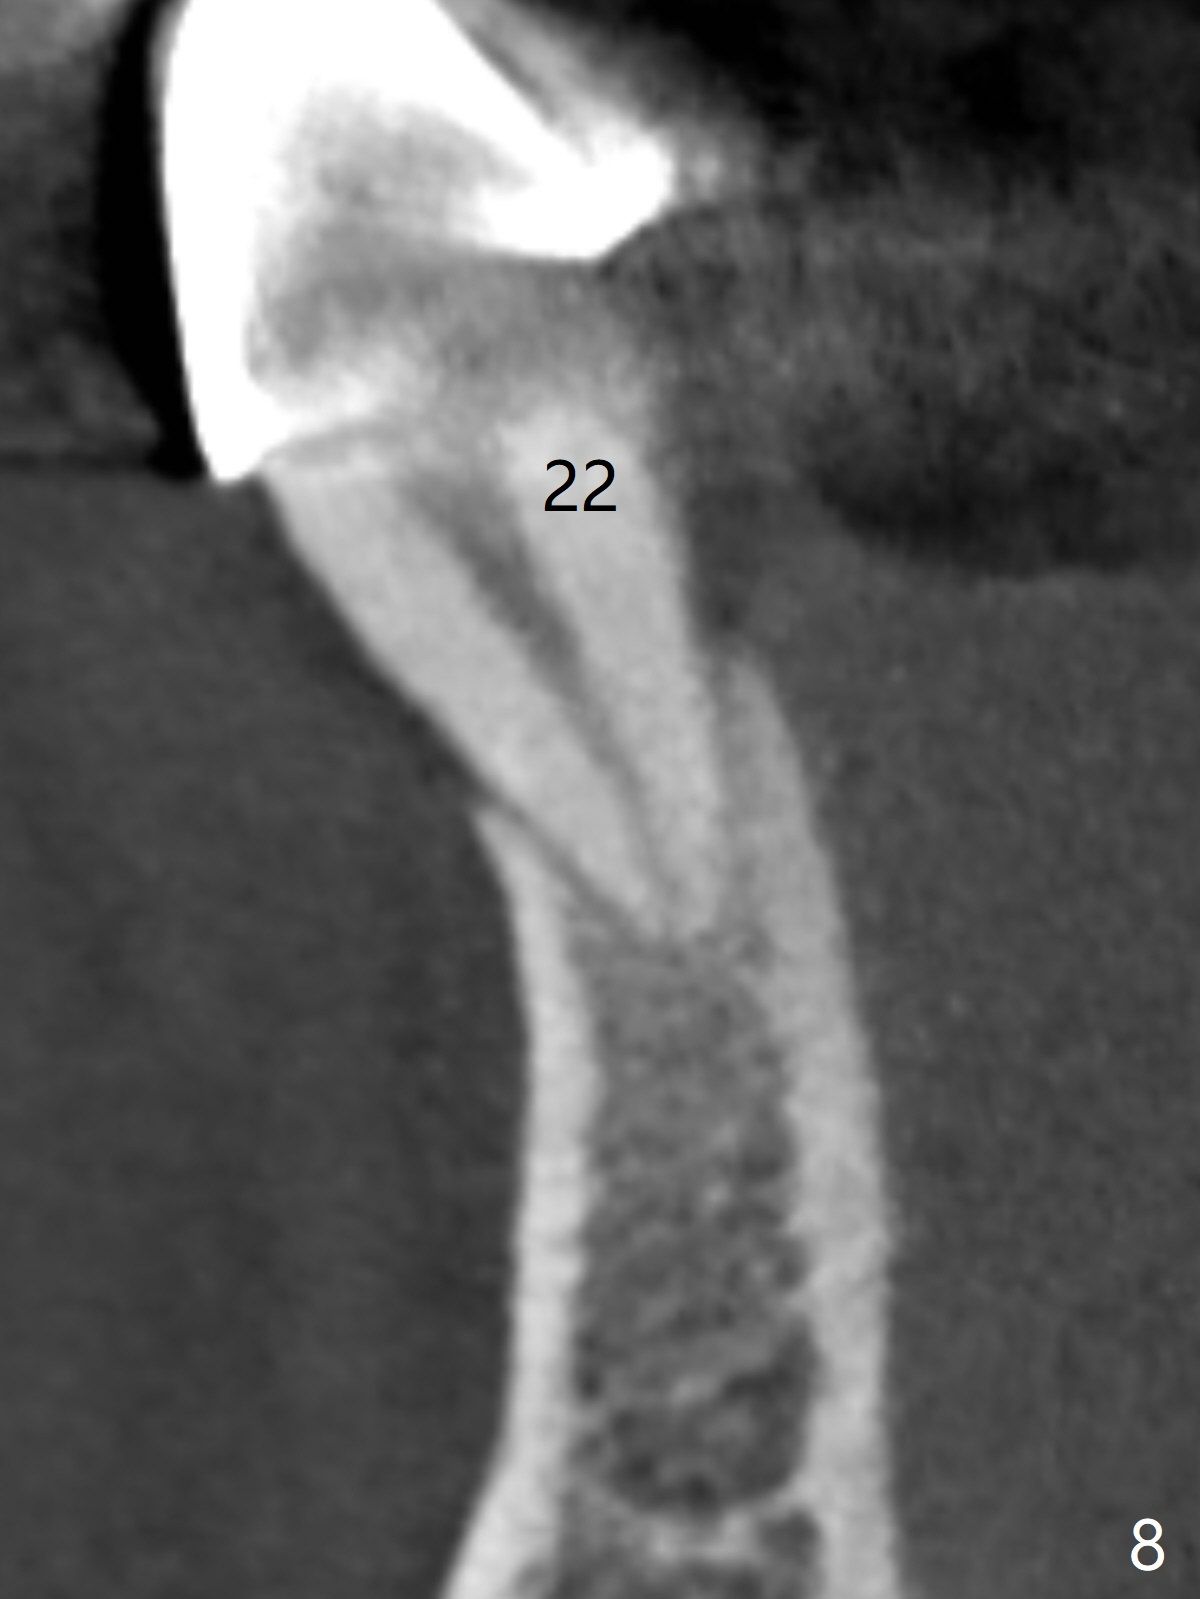

A 46-year-old man has finished upper implant placement (9-11 15 UR provisional) and wants to have lower anterior done (Long Cuff Wax up 2). The tooth #28 has exfoliated, while #22-27 FPD has mobility. It appears that the anchor tooth #22 has more severe periodontitis than that of #27. If the condition remains the same, section FPD between #22 and 23. Implants will be placed probably at #23, 26, 27 and 28. If both of the anchor teeth are non-salvageable, the possible implant will be at #22, one incisor, 27 and 28. In fact the patient requests an implant at #28.